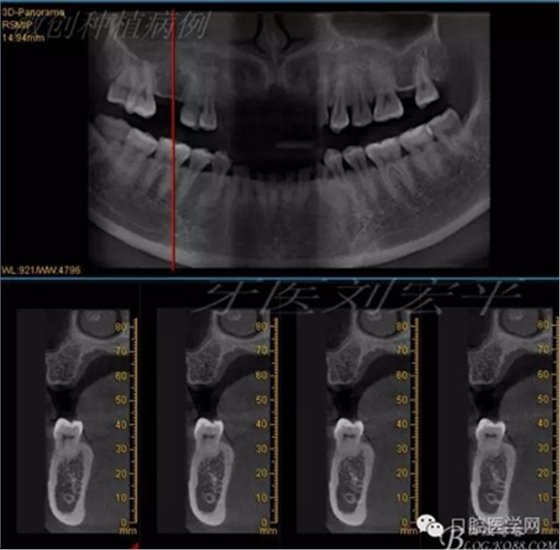

術(shù)前CT截圖,種植區(qū)骨高度及寬度充足